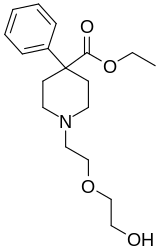

The first fully synthetic opioid was meperidine (later demerol), found serendipitously by German chemist Otto Eisleb (or Eislib) at IG Farben in 1932.[228] Meperidine was the first opiate to have a structure unrelated to morphine, but with opiate-like properties.[199] Its analgesic effects were discovered by Otto Schaumann in 1939.[228] Gustav Ehrhart and Max Bockmühl, also at IG Farben, built on the work of Eisleb and Schaumann. They developed "Hoechst 10820" (later methadone) around 1937.[230] In 1959 the Belgian physician Paul Janssen developed fentanyl, a synthetic drug with 30 to 50 times the potency of heroin.[211][231] Nearly 150 synthetic opioids are now known.[228]